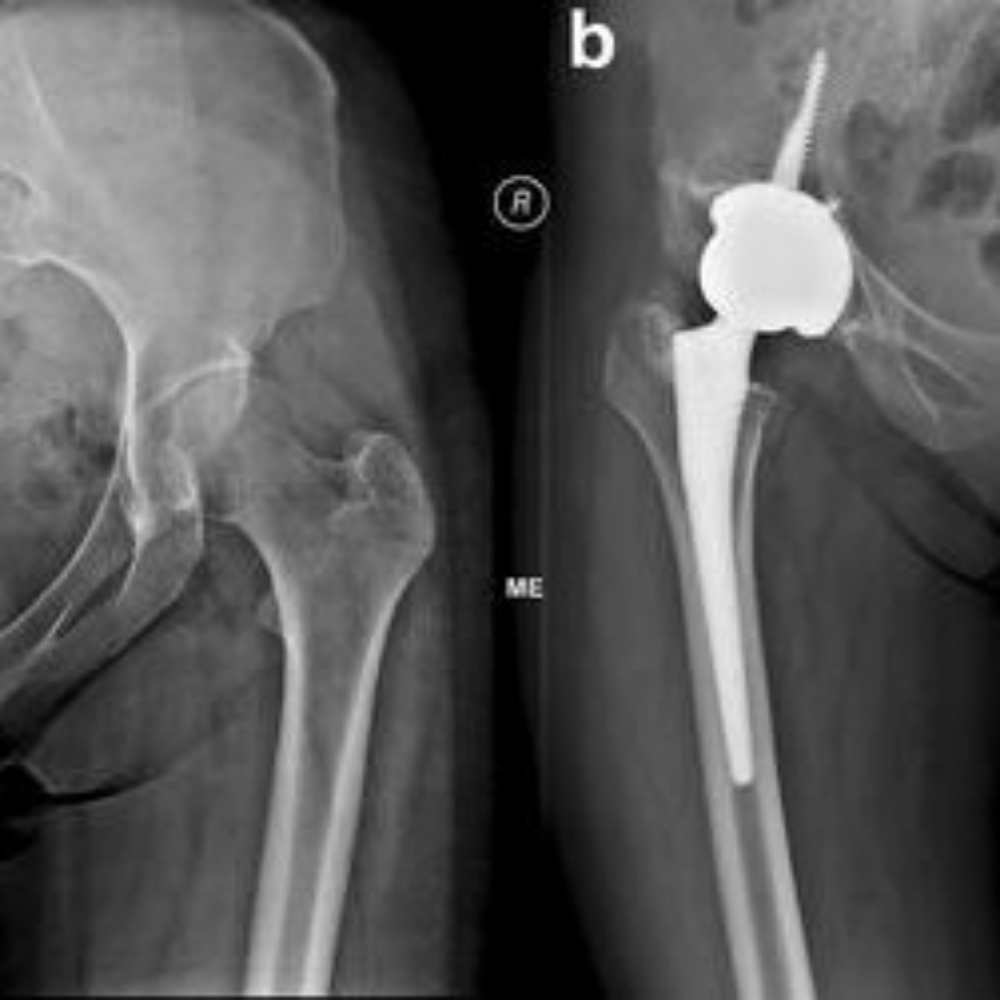

Replaces the damaged hip joint on one side with an artificial implant.

Recommended for patients with severe pain and functional limitation in one hip.

Performed when a previous hip replacement fails or wears out.

More complex due to scar tissue and implant removal.